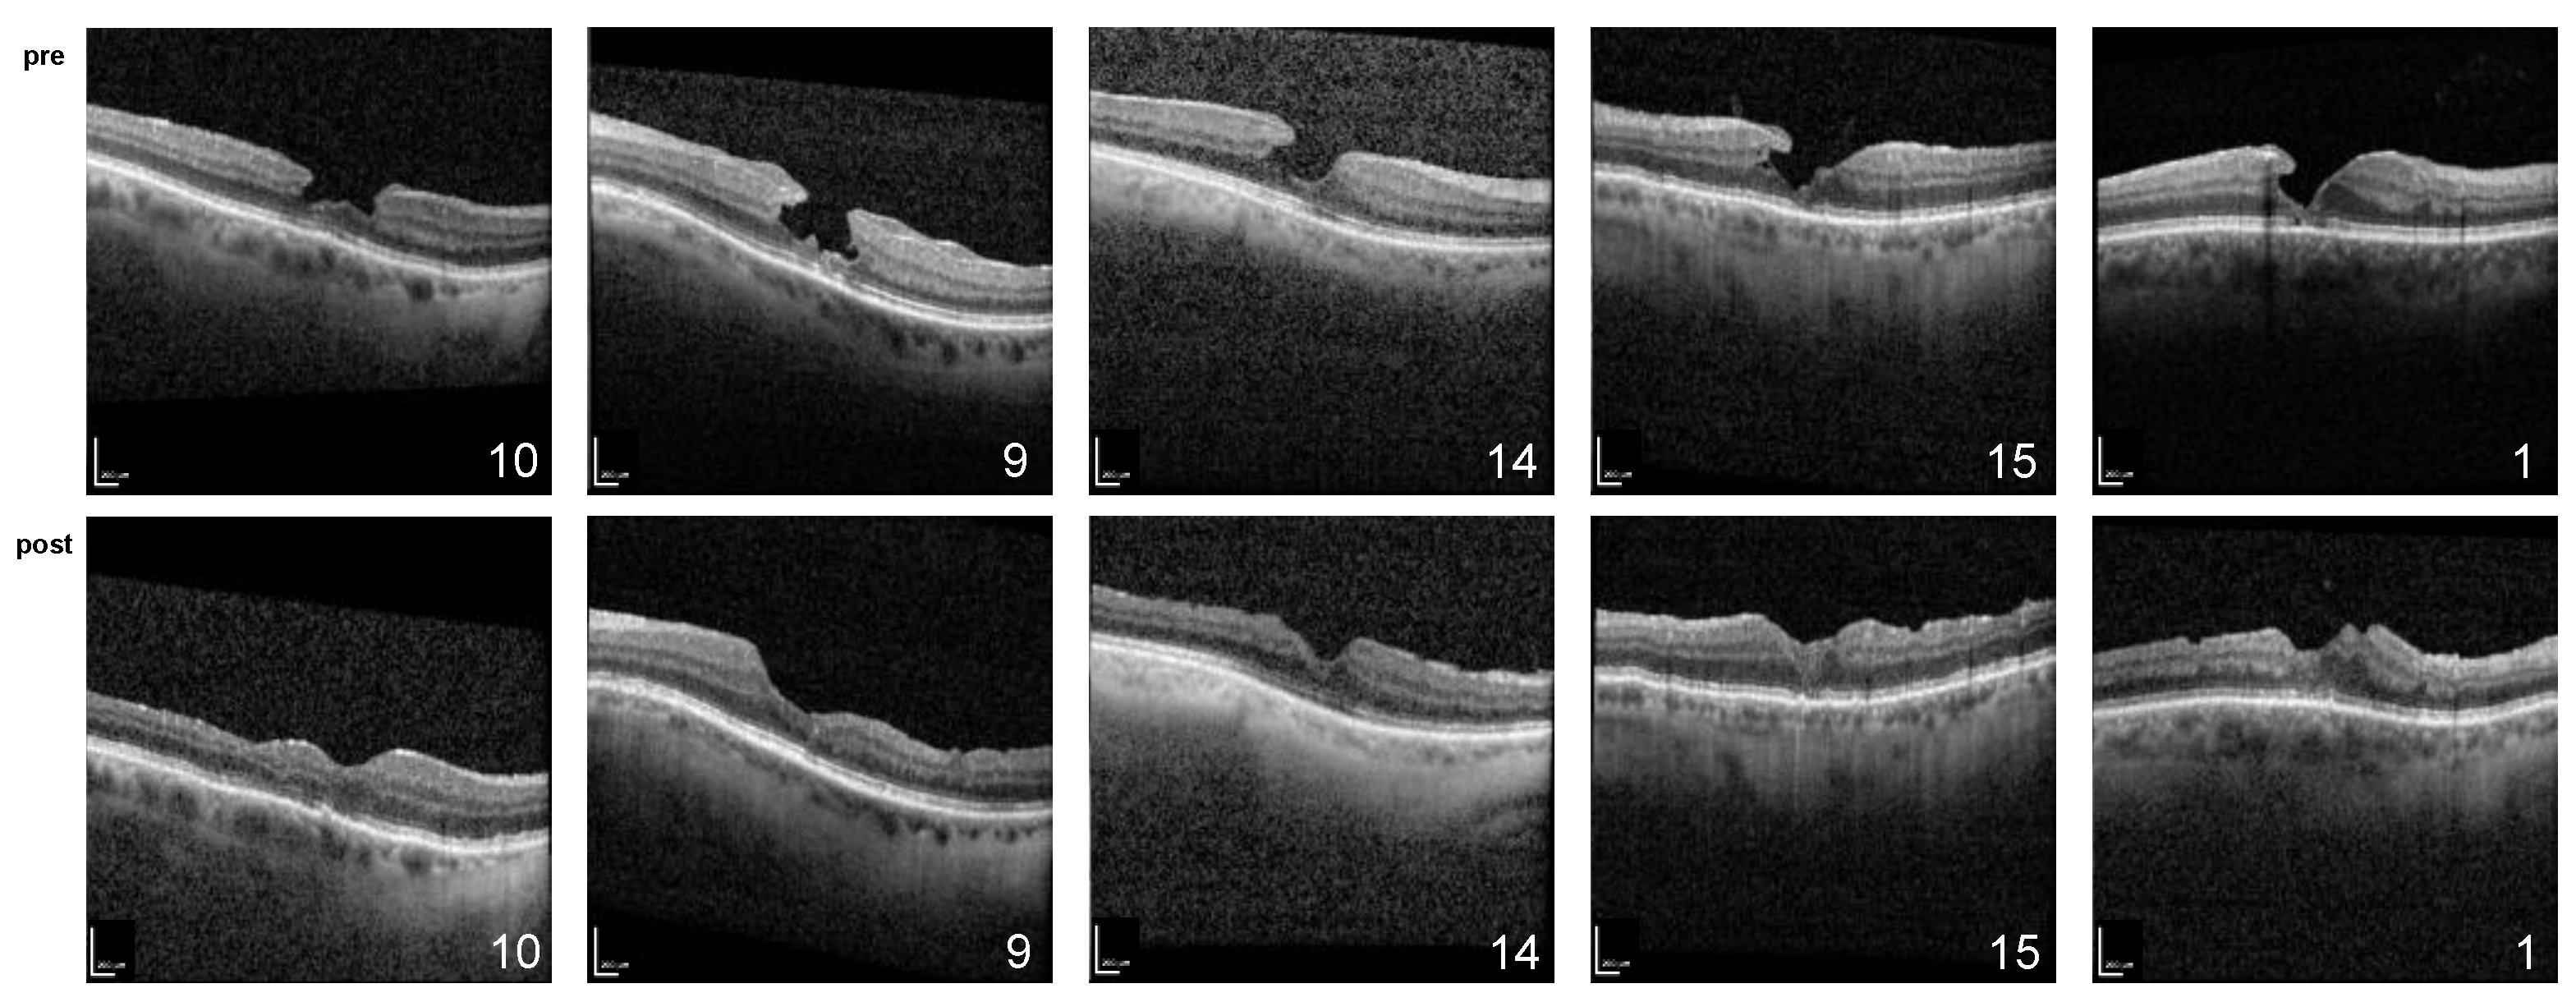

Initially, the restoration of the foveal contour with no signs of tissue loss remaining was observed in all cases (Figure 1 and Figure 2). Ellipsoid zone defects improved in 6 of 11 cases (55%). This morphology was stable during the whole follow-up period, except for in the cases of three patients, which are described below.

Figure 1.

Spectral domain optical coherence tomography of patients (ID 1, 3, 7, 9, and 10) conducted preoperatively (top) and at the most recent follow-up (bottom); scale bar = 200 µm.